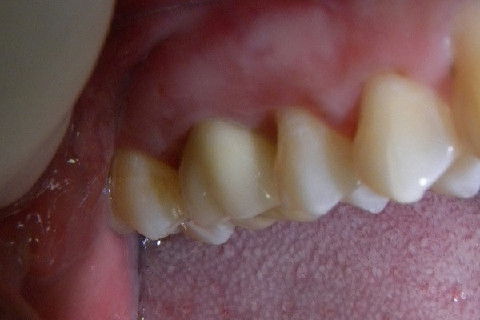

2ª CONSULTA: Coroa e-max instalada